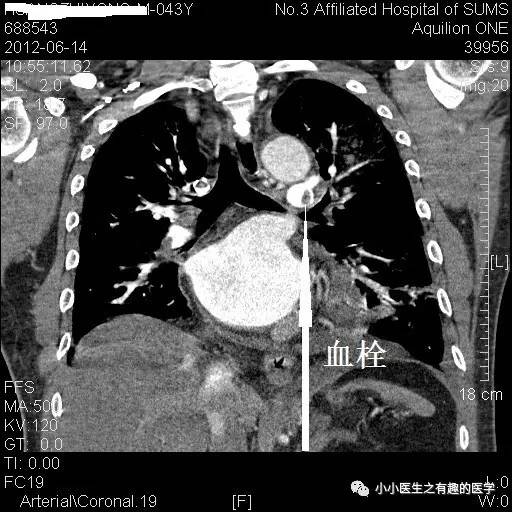

卫生部北京医院的病例。

亲们,这个胯子张的不是一般的大,可以去马戏团表演了,舞姿优美的一字马。大写的服。

亲们,这个左、右肺动脉主干几乎完全阻塞:一句话,蛋碎一地。也叫蛋碎肺栓塞,消失蛋肺栓塞,严重扯蛋肺栓塞。